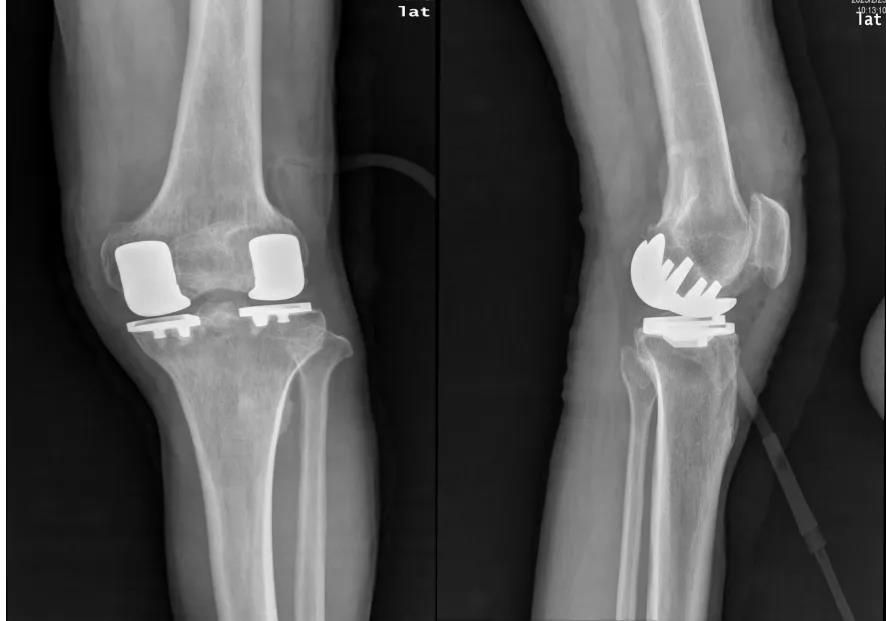

膝骨关节炎是一种常见的关节疾病,尤其好发于中老年人,缓解疼痛,减轻炎症,改善关节功能,延缓疾病进展是治疗的目的和方向。近日,玉林市中西医结合骨科医院膝关节外科团队成功完成一例双间室单髁置换术(BI-UKA),标志着我院在膝关节骨性关节炎的阶梯化治疗领域取得重大突破。此次手术采用国际先进的微创保膝技术,针对膝关节内外双间室病变患者,通过对膝关节的内外两个间室进行表面置换的手术。精准修复受损关节面,最大程度保留患者膝关节正常结构与功能,使患者术后保留良好的本体感觉,为复杂膝关节炎患者提供了更优解决方案。

70岁的男性患者双侧膝关节疼痛5年,平常连走路都困难。经检查发现左侧膝盖内外侧软骨严重磨损。经评估,所幸前后交叉、内外侧副韧带结构完整,如何让该患者“精准治疗”(只针对磨损部位修复)?医院膝关节外科团队与影像科、麻醉科等多学科专家联合讨论,为其精心制定治疗方案,决定给该患者实施双间室单髁置换术。术后第二日即实现下地行走,关节活动度达120°以上,患者生活质量得到显著提升。

※术前

※术后